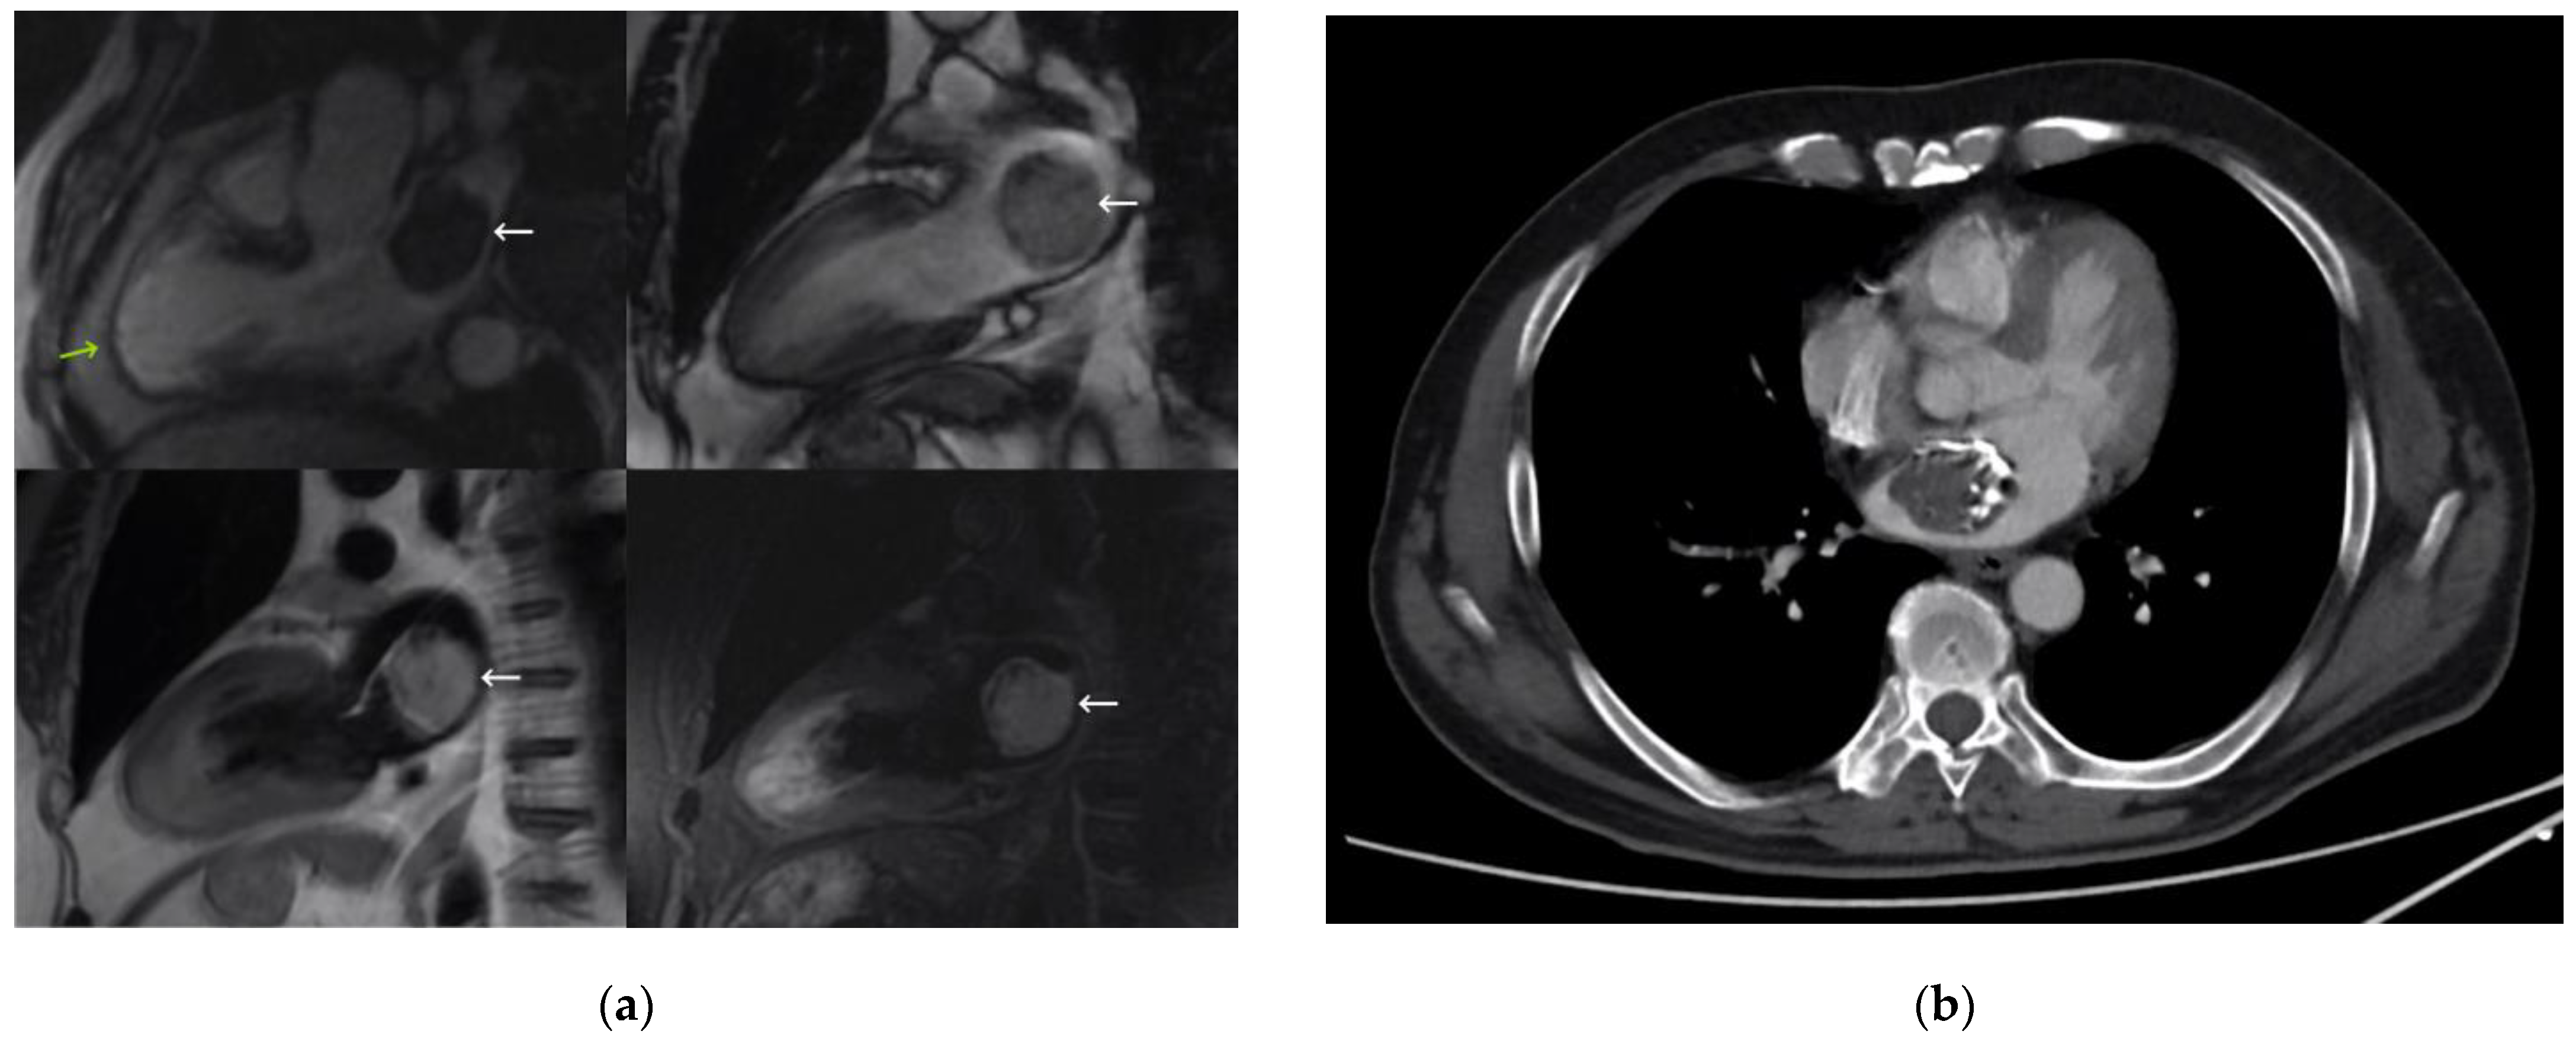

A 72-year-old man with no relevant history was admitted for chest pain and diagnosed with anterior acute myocardial infarction. Emergency coronary angiography with drug-eluting stent implantation in the mid-left anterior descending artery was performed. TTE revealed mild left ventricular dysfunction due to an apical contractile disorder, and a heterogeneous mass was incidentally found in the left atrium without compromising mitral valve function. An initial differential diagnosis of thrombus or primary neoplasia was considered, with myxoma as the main suspicion given the echocardiographic appearance and location of the mass. Anticoagulation was maintained and TEE was performed, revealing a large mass of 40 × 33 mm that was not very mobile and heterogeneous, with areas of cavitation and calcification and a wide pedicle attached to the interatrial septum in the anterosuperior region.

MRI (Figure 3) showed an anterior infarction with mild systolic dysfunction due to akinesia of all apical and mid-anteroseptal segments. It also revealed a 35-mm left atrial mass, hyperintense on T1 and hyperintense and heterogeneous on T2 images, with signal suppression on fat-saturated sequences and no enhancement after contrast administration. It had iso/hypersignal on a T2 triple inversion recovery sequence, which was suggestive of liquid content, as well as hypointense intralesional foci on all sequences, probably related to calcifications. Given the described behavior of the mass, especially the lack of enhancement after contrast administration and signal suppression in fat-saturated sequences, which have not been classically described for a myxoma, it was classified as a probable lipoma.

In a multidisciplinary approach, jointly with the Medical Oncology Department, a full-body CT scan was performed (Figure 3), which showed a mass attached to the interatrial septum by a wide and hypodense pedicle with extensive peripheral calcification. The CT ruled out satellite lesions that could indicate a malignant origin. In addition, the tumor markers were negative. Given the doubts about the benign nature of the lesion and the high surgical risk given the recent infarction, anticoagulation was prescribed, with reevaluation in 6 months with a new MRI, when the indication for resection would be reconsidered. During this time, the patient remained asymptomatic, and the cardiac mass maintained the same diameters.

Figure 3. (a) Magnetic resonance imaging showing a three-chamber view, enhancement sequence (top left), and two-chamber views, without enhancement (top right), and double short T1 inversion recovery (IR) sequence (bottom left), and T2 triple IR sequence (bottom right). The right atrial mass is marked with a white arrow, and a previous acute myocardial infarction is marked with a green arrow. (b) Computed tomography image.